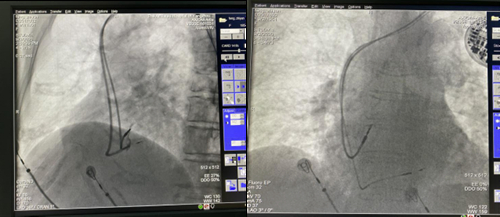

9月23日,副院长、消化内科主任丁岩冰和消化内科副主任邓彬分别为两名患者实施了POEM手术和STER手术,成功解决两位患者进食困难的问题。患者束先生,26岁。5年多来,吞咽困难、进食不畅的问题一直困扰着他。平日里进食均需要大量饮水送服,经常出现反酸、胸痛及恶心呕吐等症状。辗转就诊多家医院,未能明确原因。近日,束先生来到我院消化内科门诊就诊,经副主任医师王梅诊疗后,考虑为“贲门失迟缓”。后经上消化道造影检查,发现食管下段扩张、近贲门狭窄,成“鸟嘴样”改变,收治消化内科。结合该患者的相关检查结果,消化内科副主任邓彬、李瑶瑶博士、吴克艳博士等对其进行病情评估,确诊其为贲门失弛缓症Ⅲ型。经与患者和家属充分沟通后,在麻醉科的协助下,丁岩冰亲自为该患者实施经口内镜下食管括约肌切开术(POEM)。该手术通过在食管下段粘膜下层建立隧道后,进行食管下段环形肌和纵行肌的全层肌肉切开,历时35分钟,彻底解决患者进食困难问题,建立顺利进食的生命“隧道”。术后,丁岩冰介绍,贲门失弛缓症是食管贲门部的神经肌肉功能障碍,导致食管功能障碍引起的食管下段括约肌弛缓不全,食物无法顺利通过而滞留,可引起食管扩张。其临床表现为吞咽困难、胸骨后疼痛、食物反流以及反流引起的咳嗽、肺部感染等症状,严重患者可因长期营养障碍引起明显消瘦,生活质量差。目前POEM是针对该疾病的首选治疗方法,具有创伤小、术后恢复快、症状改善明显等优点。另一患者万女士,也因反复吞咽不畅症状,且伴有上腹部不适近日就诊。消化内科副主任肖炜明为其进行了胃镜及超声检查,发现患者贲门齿状线上方及贲门下小弯侧,两处粘膜下肿瘤,大者约2.0×1.8cm,由于肿瘤的压迫导致进食不畅,后收治我院。邓彬通过充分术前评估,与家属沟通后,运用内镜黏膜下隧道肿瘤切除术(STER),同样在食管建立进食的生命“隧道”,在瘤体上方约6cm处,分别建立两条隧道,同时挖除两个瘤体,一次性解决患者疾苦。术后,邓彬介绍,STER是在消化内科常用术式内镜黏膜下剥离术(ESD)基础上延伸出来的手术方法,主要用于切除黏膜下(包括固有肌层、浆膜层甚至消化道腔外)的肿瘤,包括脂肪瘤、平滑肌瘤、间质瘤等等。该术式通过从病变上方的黏膜层开始,建立粘膜下隧道,可保持粘膜层完整,并保持消化道功能的完整性,不影响患者生活质量。近年来,我院消化内科、麻醉科、病理科、影像科、普外科、胸外科、内镜中心及手术室护理团队紧密合作,已成功对多种消化道疾病包括消化道早癌及癌前病变、贲门失弛缓、胆总管结石、消化道梗阻、小肠粘膜病变、食管胃底静脉曲张破裂出血等实施内镜下微创手术治疗,其创伤小、恢复快、费用低等特点,既解决患者病痛,同时也减轻患者经济支出。